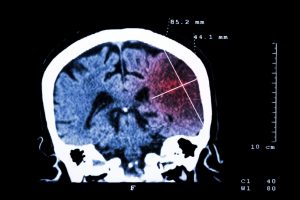

Ischemic stroke risk is linked to traumatic brain injury (TBI), independent of other factors. Lead study author James F. Burke explained, “Both stroke and traumatic brain injury are common, costly, and leading causes of severe disability in adults, and approximately 20 percent of strokes occur in adults under age 65. A large proportion of stroke risk is unexplained, especially in the young, so if we can identify new risk factors, we have the potential to prevent more strokes and improve outcomes.”

The study included 435,630 people with traumatic brain injuries and 736,723 without. Over the course of 28 months, 11,229 people experienced ischemic stroke. Of the TBI group, 1.1 percent had a stroke, compared to only 0.9 percent of those with trauma with no brain injury.

After adjusting for stroke risk factors, those with brain injuries were 30 percent more likely to experience an ischemic stroke, than those with other traumas but no brain injury.

Burke added, “While the stroke risk of one person with TBI is small, the overall link between TBI and stroke was substantial — as large as the link between the strongest stroke risk factor, high blood pressure, and stroke. If further research establishes TBI as a new risk factor for stroke, that would stimulate research to help us understand what causes stroke after TBI and help us learn how to prevent these strokes.”